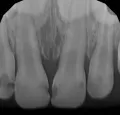

У моей дочери, возраст 1 год 6 месяцев, кариес эмали верхних шести зубиков, четыре передних резца и два жевательных. Кариес сейчас выглядит как желтые круглые бороздки на зубках. Были у детского стоматолога - сказала ставить пломбы под наркозом. Очень не хочу лечить зубки под наркозом, так как сомневаюсь в безопасности самого наркоза.